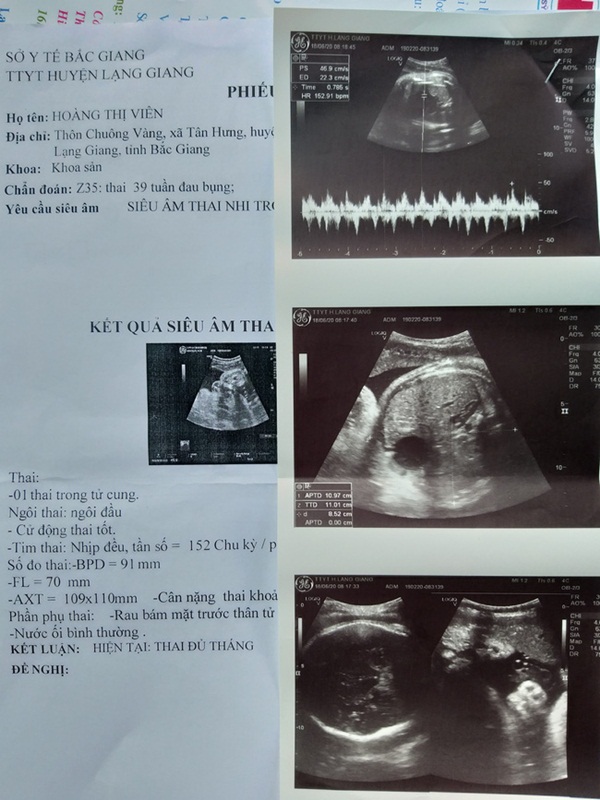

Qua khám, siêu âm, xét nghiệm, bác sĩ kết luận: Thai 39 tuần, lần 3 chuyển dạ đẻ, mọi thông số trong giới hạn bình thường. Theo dõi chuyển dạ (trong thời gian từ 16 giờ đến 22 giờ ngày 24/6), chị Viên tỉnh táo, tim thai tốt, cổ tử cung mở từ 1 đến 3 cm, ngôi đầu, không có biểu hiện bất thường.